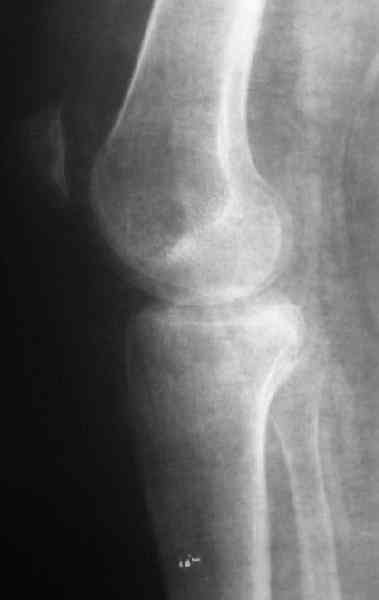

Обратился больной 46л. 3-месяца назад в каком-то городке Дальнего Востока упал с высоты, сделана Р-графия, наложена гипсовая повязка, от предложенной операции отказался и уехал домой, дальше где и как лечился, не говорит.

Ходит при помощи двух костылей, жалобы на боли при нагрузке, в покое и при движении, без нагрузке боли нет, разгибание 175 гр, сгибание 90 гр, симптомов повреждения связочного аппарата к/с не определяется, от предложенного артродеза пока отказывается.

По тактике лечения, более импонирует второй вариант, но наружная плато расколота и туда при нагрузке внедряется н/мышелка бедра, поэтому после дистракции как репонирвать: или стяжными винтами, или изогнутами спицами или субхондральная костная пластика?

У пациента основной проблемой является импрессионый перелом наружного мыщелка, уже неправильно сросшийся, по-видимому. Аппаратом закрыто можно только подправить угол на уровне метадиафиза. Что

улучшит разве что внешний вид конечности, но не решит основной проблемы - грубой деформации суставной поверхности.